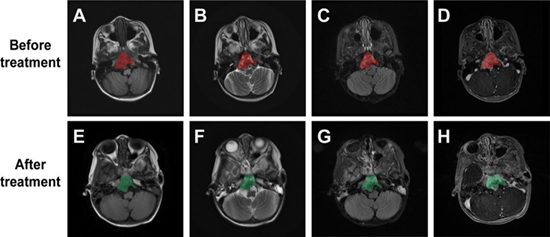

分化差脊索瘤是一种罕见的高恶性肿瘤,常发生于颅底、脊柱及骶尾部等复杂部位,临床症状隐匿、复发率高、预后差。由于肿瘤紧邻重要神经、血管及脑干区域,传统放疗在提高剂量时往往受限于周围正常组织耐受性,难以兼顾疗效与安全。

质子治疗凭借其独特的布拉格峰(Bragg Peak)物理特性,能够在精准聚焦肿瘤靶区的同时显著减少周围组织损伤,为这类复杂肿瘤的精准放疗带来了可能。

河北一洲肿瘤医院肿瘤内科主任高建芝带领团队在 Discover Oncology 发表的最新研究《19例分化差脊索瘤不同治疗模式临床病例分析》表明:在19例确诊患者中,采用“手术+质子放疗+化疗/靶向/免疫”联合方案后,疼痛、视觉障碍、呼吸道梗阻等主要症状明显改善,病灶体积缩小,局部控制率提高,总生存期与无进展生存期较以往单一治疗模式显著延长。

这一结果验证了以质子治疗为核心的多模式综合治疗在提高治疗安全性和长期预后方面的临床价值,也为今后类似高难度肿瘤的治疗提供了可复制的临床路径。